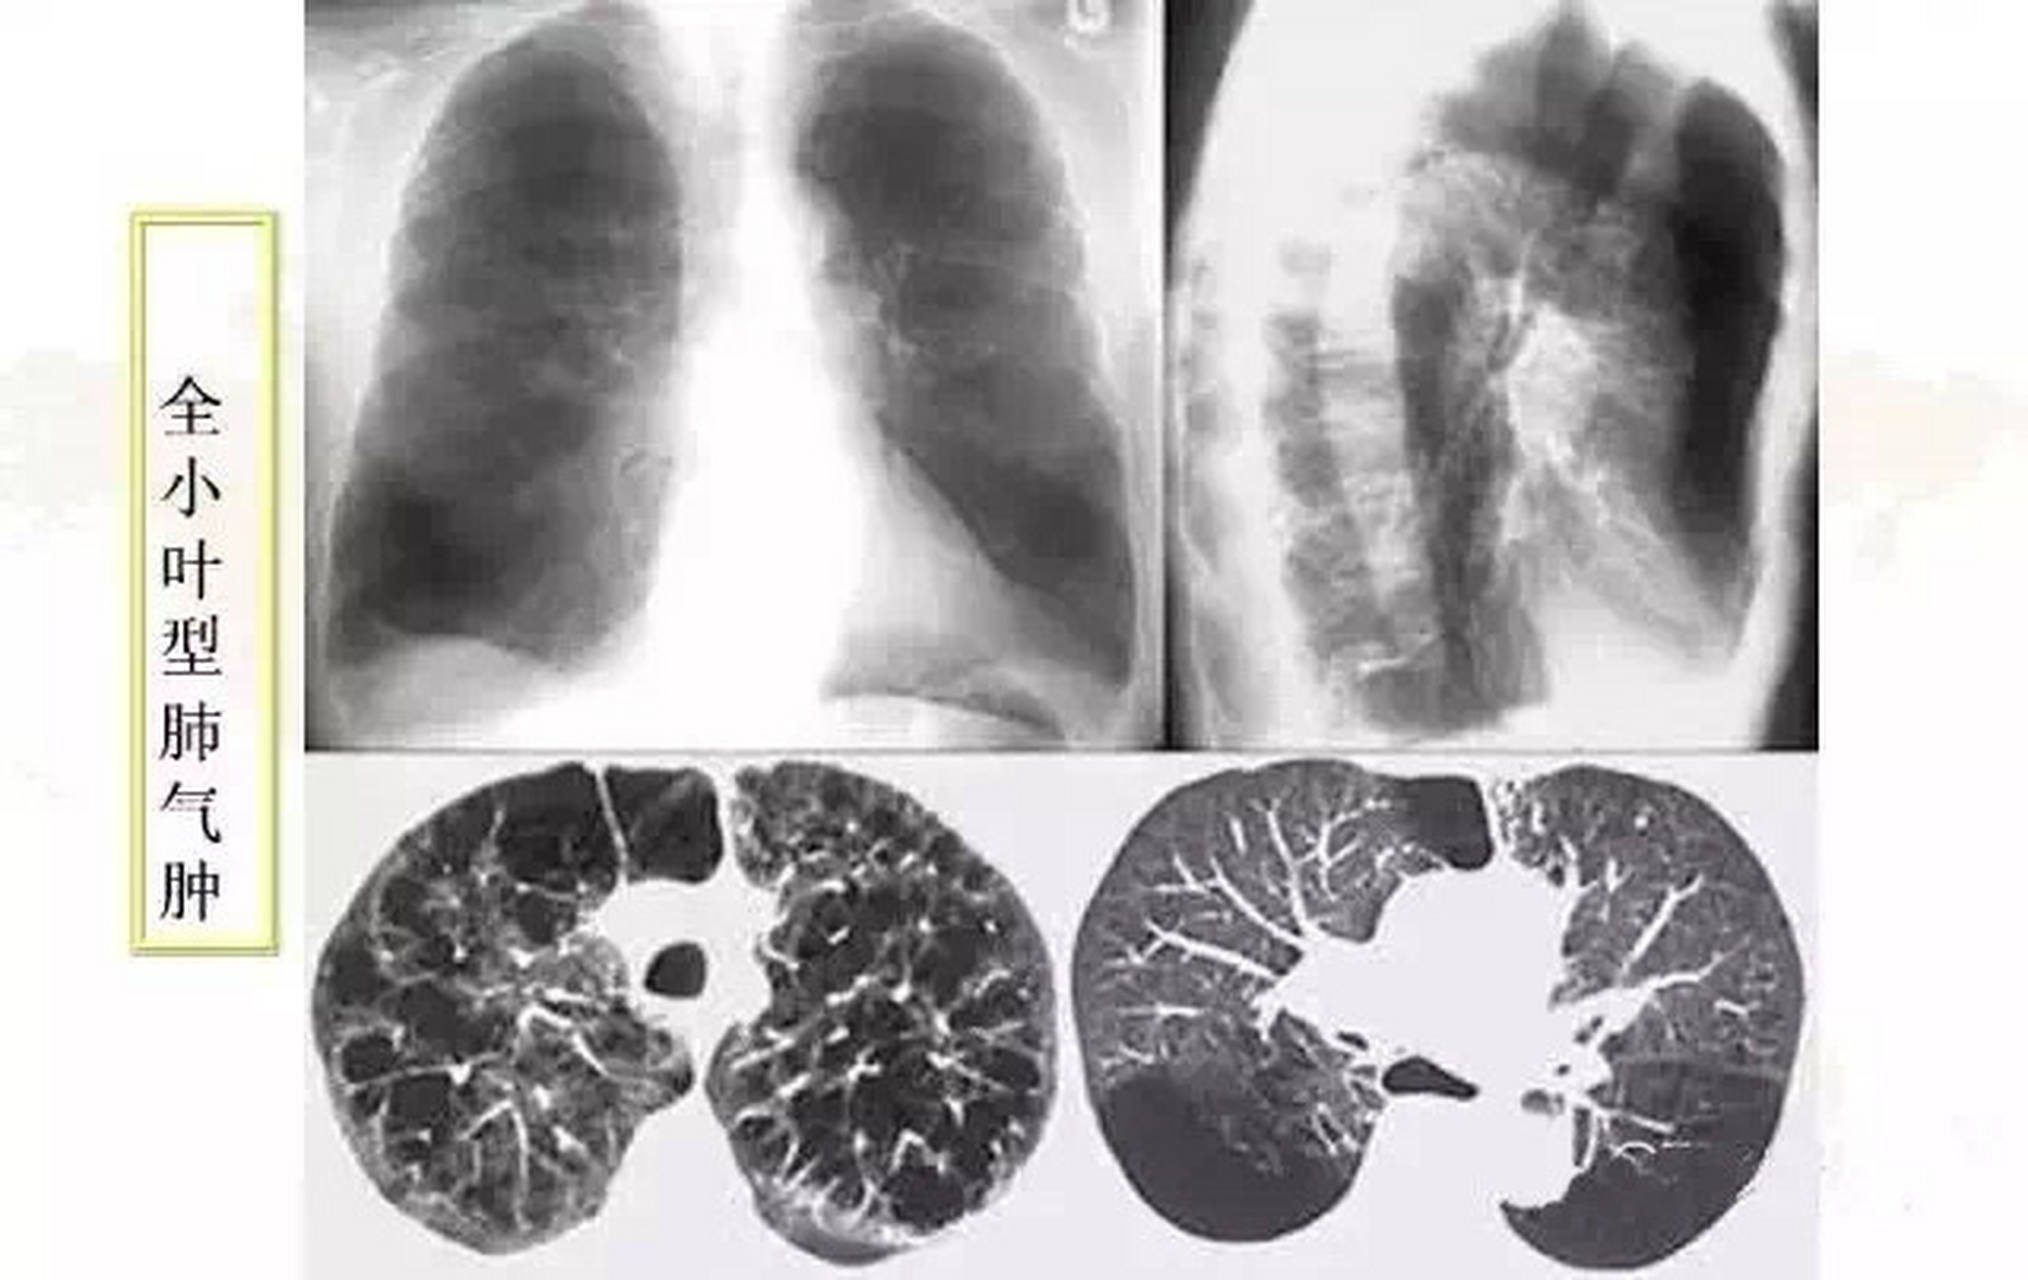

肺气肿ct分型